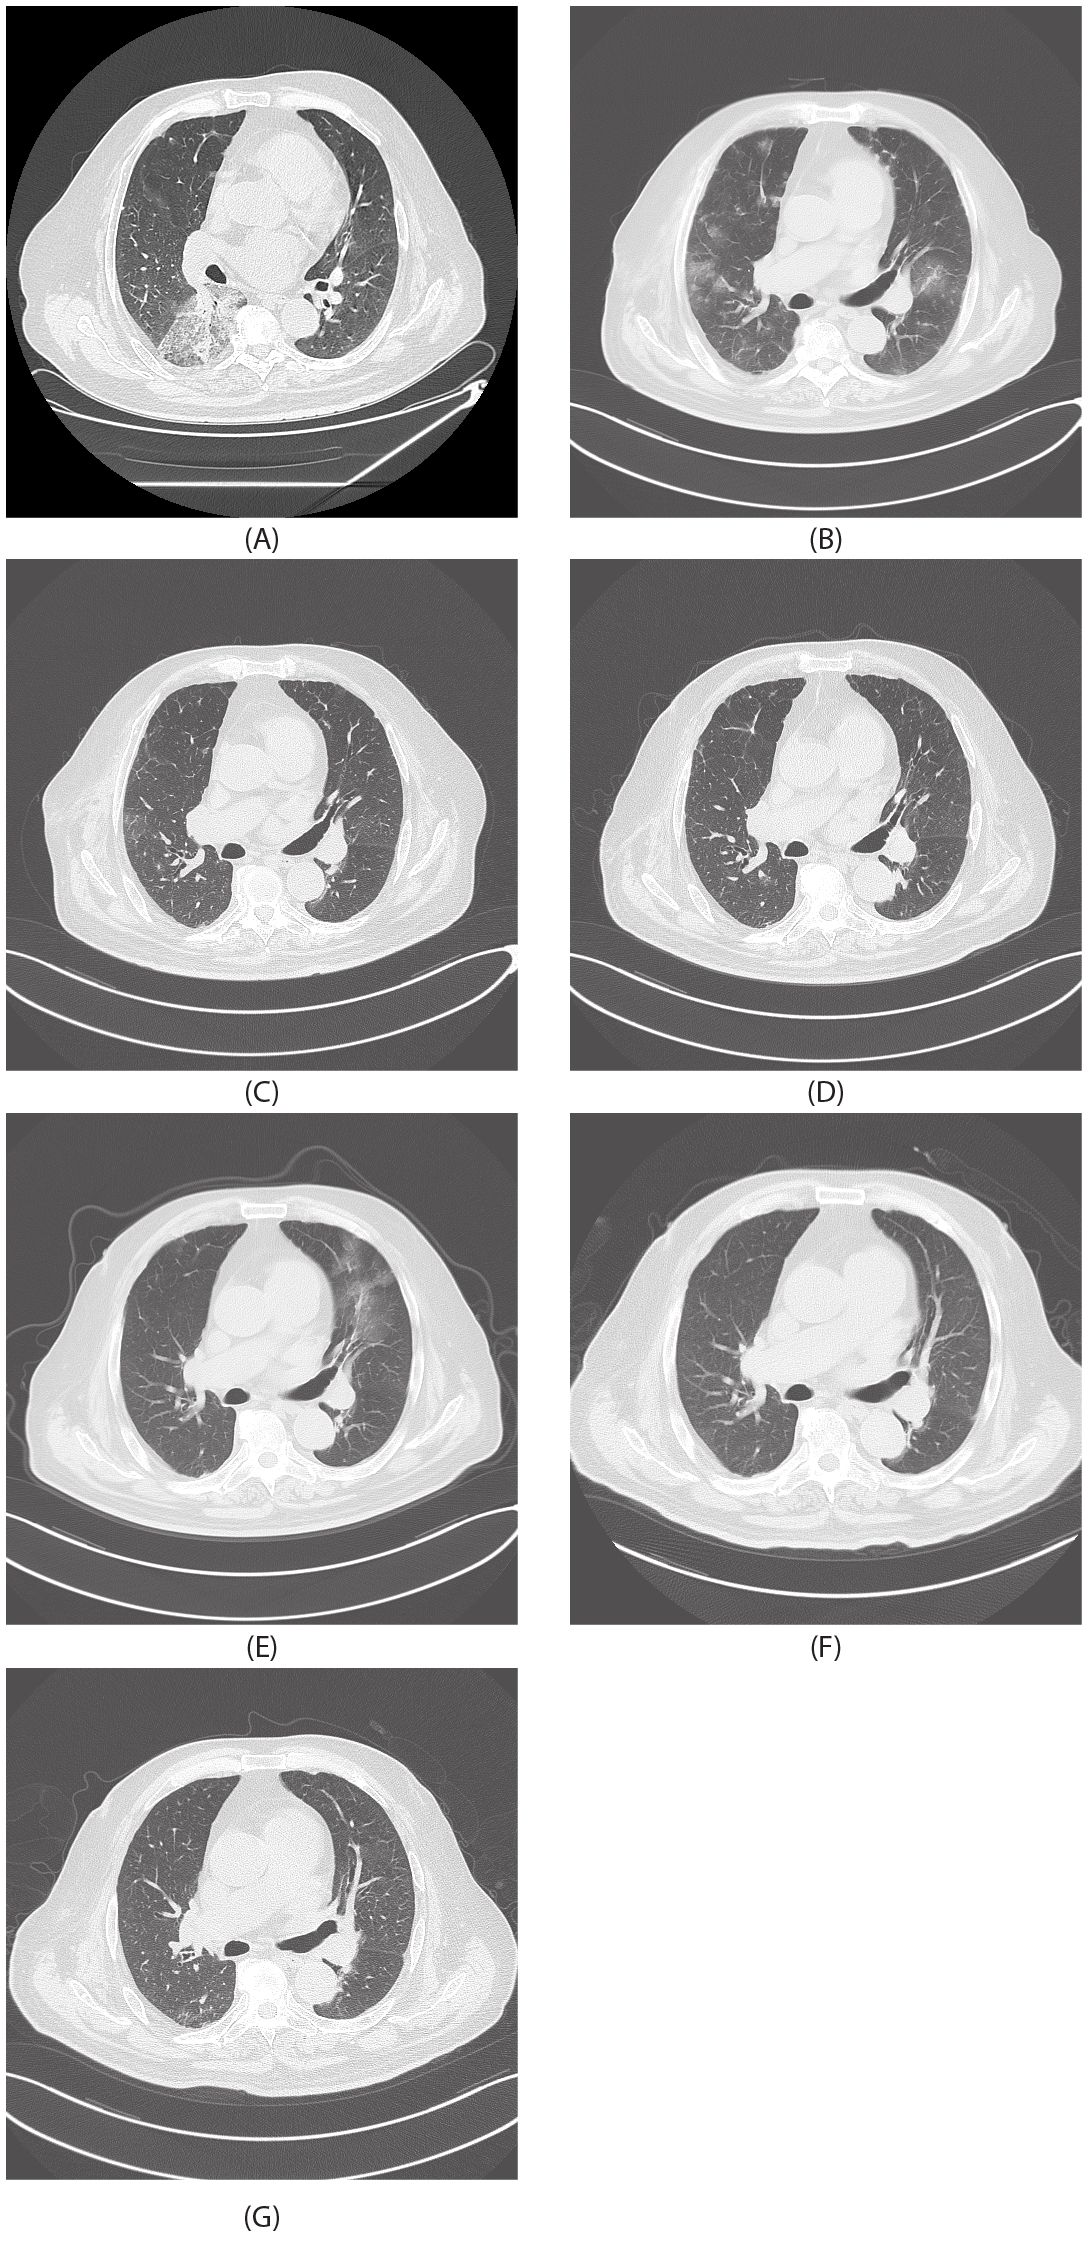

Background: Pulmonary epithelioid hemangioendothelioma (PEH) is an exceedingly rare vascular tumor, presenting a significant challenge due to its limited treatment options.Immunotherapy in combination with chemotherapy emerges as a potential frontier,yet the understanding of its application in PEH remains in its infancy. Methods:A male patient initially faced misdiagnosis as having aspergillosis.Through histopathology and immunohistochemistry,a definitive diagnosis of PEH was later established.The treatment journey involved surgical resection,followed by chemotherapy with albumin-bound paclitaxel and carboplatin,and finally immunotherapy with sintilimab. Results:A remarkable radiological improvement was observed post-sintilimab administration,leading to disease stabilization. Significantly,this is the first-ever report of the efficacy of sintilimab in PD-L1-high PEH,filling a critical gap in the existing literature. Conclusion:This case not only underscores the potential of sintilimab in PD-L1-high PEH but also sets a precedent for further exploration of immune checkpoint inhibitors in this rare disease. Translational Relevance: For the first time, we provide concrete evidence of sintilimab's activity in PD-L1-high PEH.This finding holds great promise,suggesting that immune checkpoint inhibitors could be a game-changer in the treatment of selected vascular sarcoma subtypes. Additionally,considering that about 90% of PEH cases harbor the characteristic WWTR1-CAMTA1 fusion gene,we hypothesize that this fusion might disrupt the normal immune-surveillance mechanism. It could potentially lead to the down-regulation of antigen-presenting machinery on tumor cells,making them less recognizable to the immune system. Alternatively,it may trigger the secretion of immunosuppressive cytokines in the tumor microenvironment,dampening the activation of immune effector cells.Further research is urgently needed to validate this hypothesis.